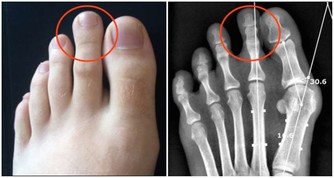

缺鐵性貧血是小細胞低色素性的貧血,放在顯微鏡下看我們血液中的紅細胞,顏色很淡,形狀也比正常情況下小很多。缺鐵性貧血的發病率非常高,在我國,差不多每5位女性中就有1個是缺鐵貧的患者。